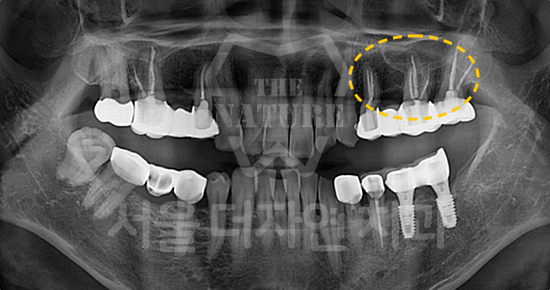

#Full Mouth Implants

• BEFORE: 2022.12.15

• AFTER: 2023.02.23